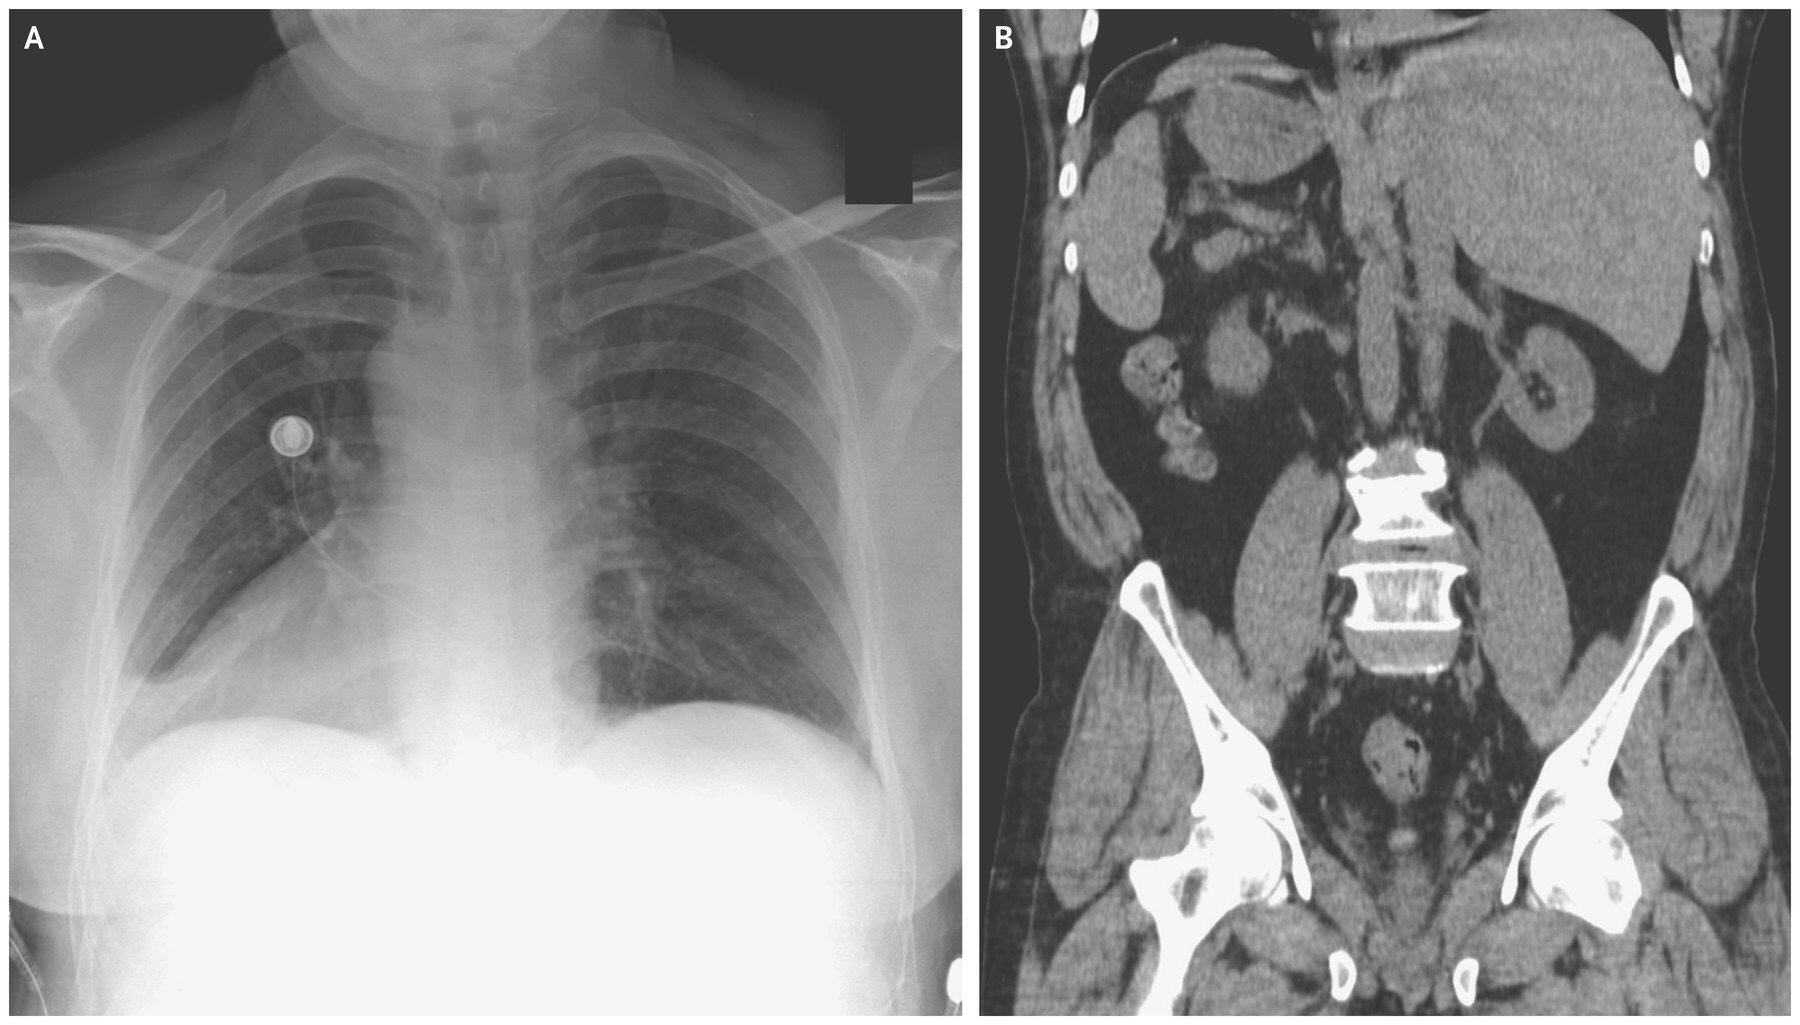

Транспозиция внутренних

Транспозиция внутренних 116 фотографий